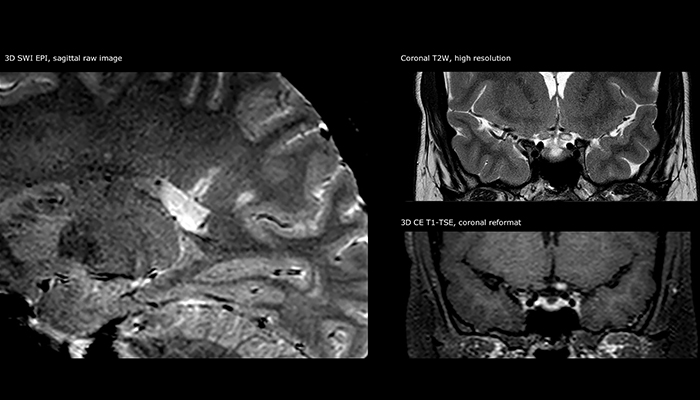

Imaging MS in brain

For MS imaging in the brain, Dr. Savatovsky uses 3D FLAIR as the basic sequence to visualize the lesions and assess the situation and lesion load. “We count the lesions in each location to determine if the criteria of the disease are fulfilled. We use a T2-weighted sequence because our neurologists are used to it. We compare the lesion load on FLAIR with a 3D T1 post-contrast sequence to help us determine whether lesions are old or new. We typically administer the contrast before the patient enters the machine because it shortens the examination time and allows to visualize active lesions that tend to be more visible after several minutes. When a differential diagnosis is difficult, we add sequences such as susceptibility imaging, because some focal MS lesions have a small vein in the center[3].”